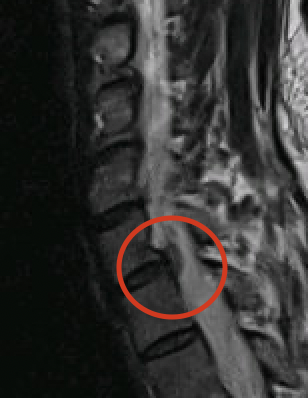

Het ideale onderzoek is een NMR (=MRI). Het levert ons de beste beelden en gebruikt geen nadelige X-stralen. Soms wordt ook een CT scan van de nek gevraagd.

Discus hernia betekent in het Nederlands breuk (= hernia) van de tussenwervelschijf (= discus). Een tussenwervelschijf bestaat immers uit een centraal zacht gedeelte en een omliggende ring. De breuk ontstaat in de buitenste ring waardoor het zachte gedeelte naar achter schuift en druk geeft op het ruggenmerg of zenuwen. Hierdoor kan pijn in de arm ontstaan. Een hernia kan ook aanwezig zijn zonder symptomen en moet dan ook niet verder behandeld worden.

Aan de linker zijde van de hals wordt een dwarse insnede gemaakt van ongeveer een 3-tal centimeter en dit ongeacht of uw hernia zich aan linker of rechter zijde bevindt. Tussen de spieren door bereiken we de wervelkolom. De tussenwervelschijf wordt in totaliteit verwijderd, inclusief de hernia welke zich in het ruggenmergkanaal bevindt. De tussenwervelschijf wordt nu vervangen door een kooi gevuld met botvervangmiddel vermengd met beenmerg dat we thv de bekkenkam met een dikke naald hebben genomen. Als laatste stap wordt er een plaatje bevestigd aan de voorzijde.